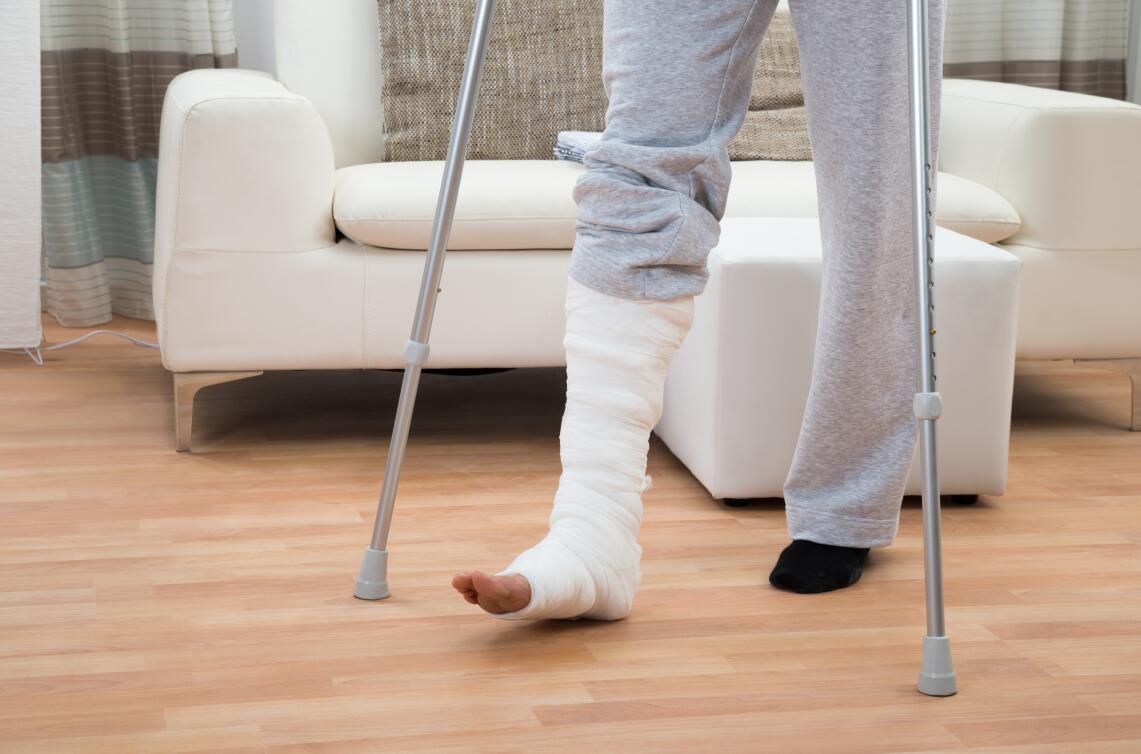

第三,康复训练,在不影响骨折制动和骨折愈合的前提下,患者应该尽早地开始康复训练,康复训练可以使肢体的关节功能得到很好恢复,同时增强肌肉的力量,增加骨折愈合的速度。

骨质疏松性骨折康复中应该注意什么?

在骨质疏松性骨折的康复中,预防跌倒特别重要。我们可以通过以下措施来降低患者发生跌倒的概率: